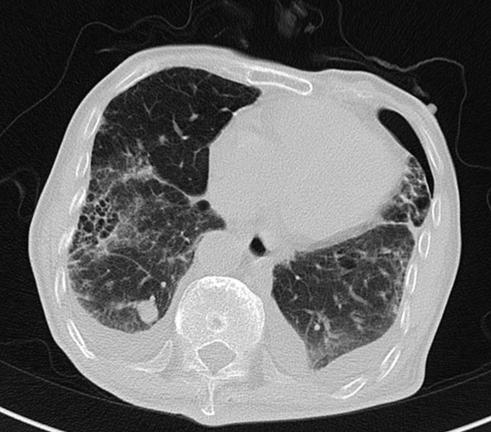

2020-01-08查胸部CT:双肺间质纤维化伴双肺气肿,双肺炎症,伴支气管扩张,右肺上叶结节样影,性质待定,双侧胸腔积液,纵膈多发肿大淋巴结,主动脉及冠状动脉硬化。

△ 2020.01胸部CT